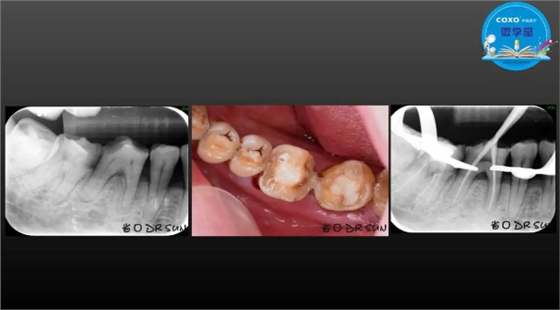

主讲:孙书昱

主任医师,牙体牙髓副主任, 广东省口腔医院牙体牙髓科 主任医师。2003年硕士研究生毕业,研究方向为牙体牙髓病学,擅长于牙体牙髓病的诊断、龋齿、牙髓炎、根尖周病的治疗以及前牙美容修复。